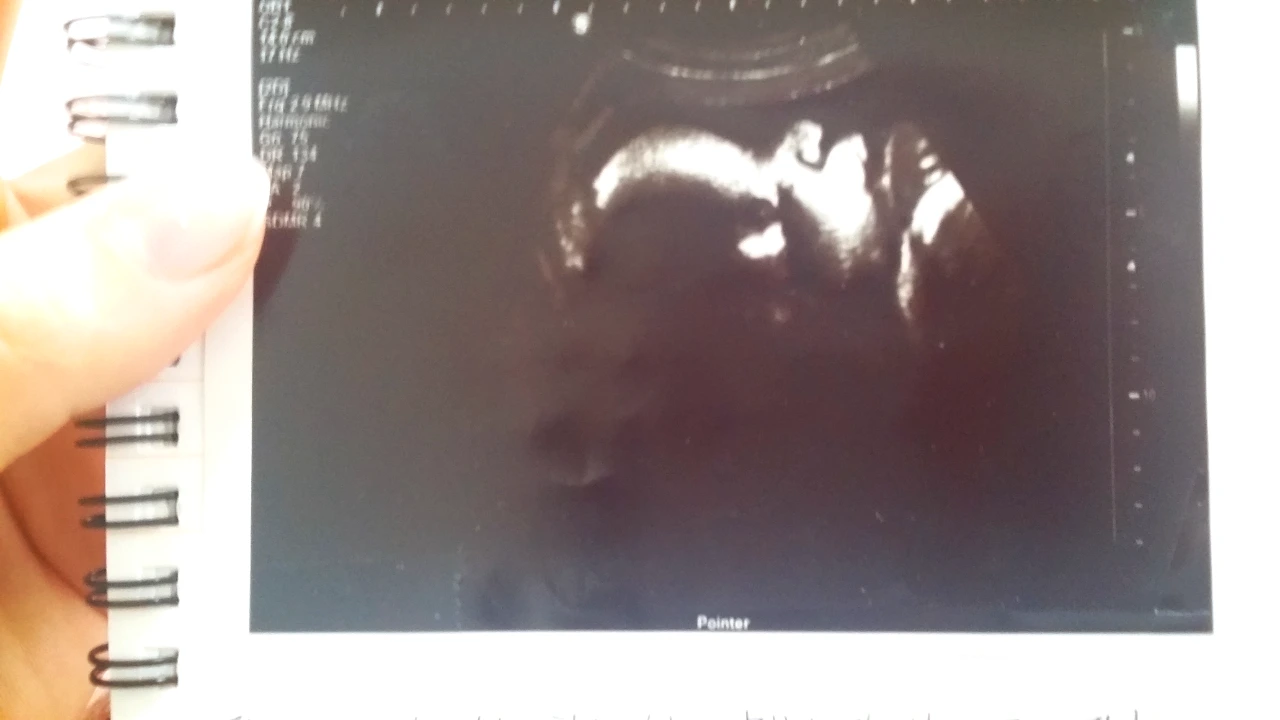

이미 초음파로는 한 화면에 아기가 잡히지 않을만큼 커진 은똥이는 아직 준비가 되지 않은듯 했다.